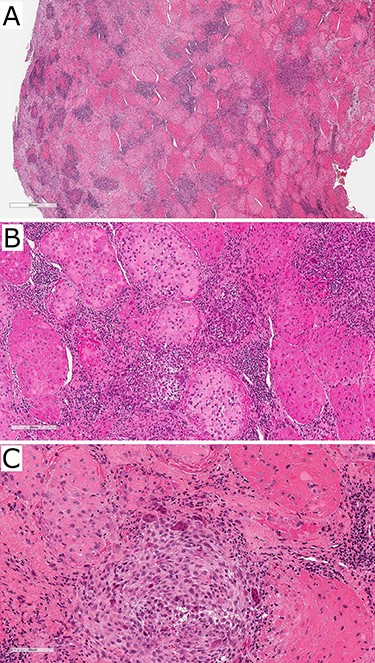

The patient was regularly reviewed reporting no improvement to stiffness on mouth opening. At her 3-month post-operative review, she complained of worsening stiffness to mouth opening. A follow-up CT of the TMJs portrayed extensive progressive bony erosion to the mandibular condylar head. This provoked a discussion with the pathologist to reconsider the diagnosis of the previously sent specimen. A histopathological revision reported a chondroid fibrohistioctyic lesion with overall features more in keeping with PVNS with chondroid metaplasia (Fig. 3).

Photographs of haematoxylin and eosin-stained slides of the resected tissue sample showing fibrohistioctyic areas in addition to cartilaginous nodules. Magnification (A) ×94, (B) ×375, (C) ×750.